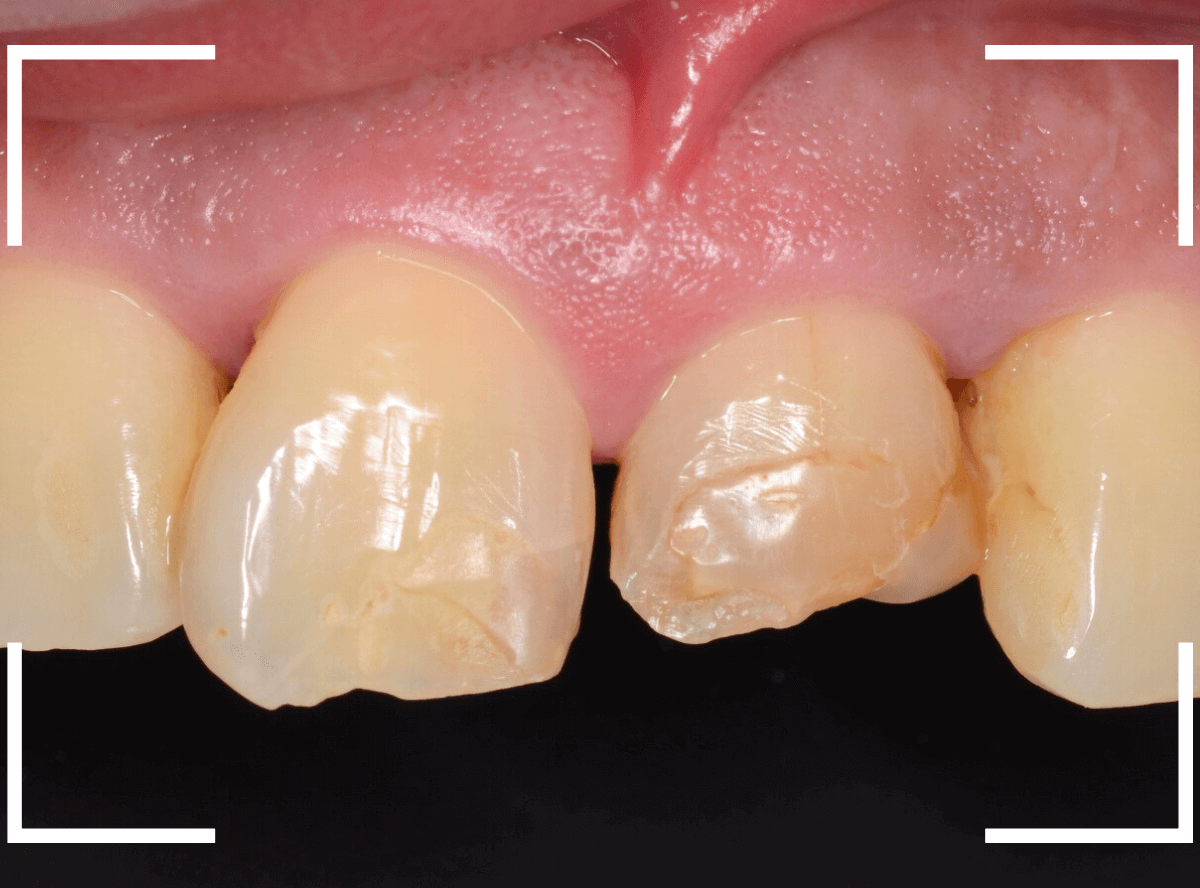

Case.3「前歯がいつも欠けてしまう」というケース

今回は、前歯につめたレジンが、毎回、すぐに欠けてしまうので直してほしいと来院された患者さんのケースです。

お口を閉じてもらうと、下のがレジンをつめたを突き上げて当たってしまうようです。

これでは、すぐに外れてしまっても仕方ありません。

治療を変える必要がありそうです。

レントゲン写真上では、歯は問題なさそうでしたが、隣の歯に比べてやけに変色しているので「怪しい」と、歯の神経を調べてみると、神経が死んでいました。

下の歯が常に突き上げている刺激が原因で、死んでしまったのかもしれません。

また、歯の周りの歯石も多く、歯周病も進行気味でしたので、